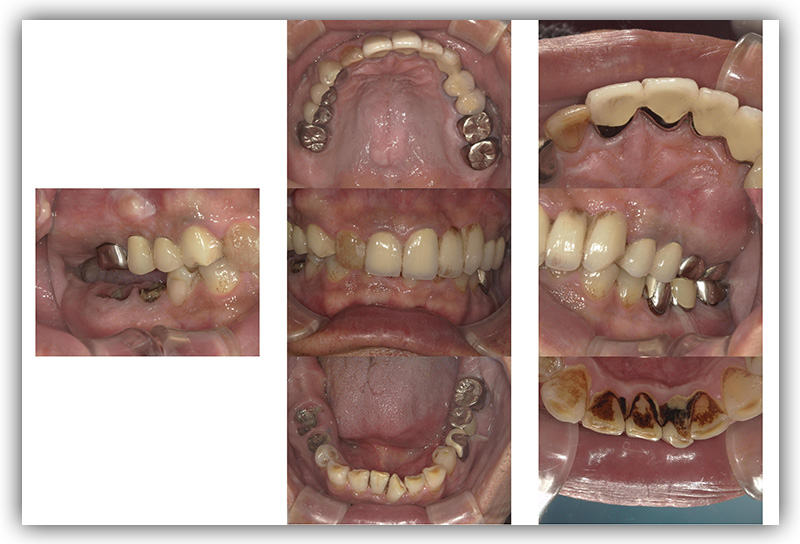

CASE_02

60代男性(インプラント)

- 患者さん情報(年齢・性別)

- 60代 男性

- 主訴

- 被せものが外れたところをインプラントにしたい

- 治療箇所

- 2箇所

- 治療方法

- インプラント

- 費用

- 約86万円

- 治療期間

- 約半年